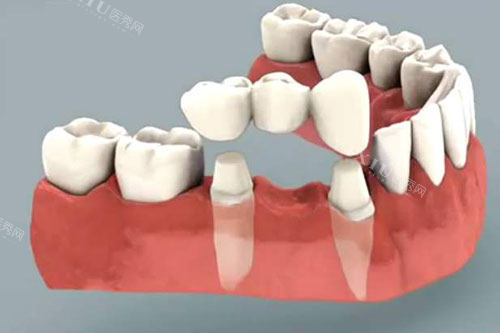

牙冠治疗过程示意图

三、牙冠修复的“底层原理”:为什么戴冠能防裂?

核心原理:牙冠通过“包括裹保护”分散咬合力,避免牙体直接受力,同时封闭根管口防止再感染。

1. 牙冠的“力学保护”:分散咬合力

戴冠后:牙冠将咬合力传递至整个牙冠结构,减少局部应力集中

实验数据:戴冠牙齿的抗折强度是未戴冠的3.2倍(来源:《口腔修复学》期刊)。